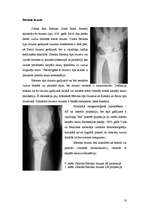

Visizplatītākie no apakšdelma lūzumiem ir radius distālās metaepifīzes lūzumi, t.s. radius lūzumi tipiskā vietā, kas izceļas ar lielu lūzuma veidu dažādību un diezgan bieži kombinējas ar citiem bojājumiem plaukstas locītavas rajonā.

Apakšdelma distālās trešdaļas lūzumus pēc būtības var uzskatīt par plaukstas locītavas proksimālās daļas bojājumiem. Tādēļ tie var kalpot par iemeslu fukcionāliem traucējumiem plaukstas locītavā ne tikai nepareizas saaugšanas gadījumā, bet arī tad, kad repozīcija ir veikta savlaicīgi un kvalitatīvi, un fiksācija bijusi adekvāta.